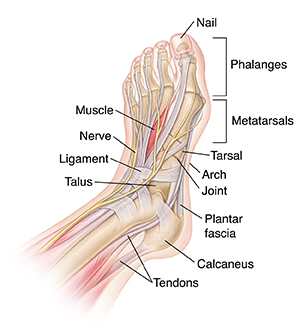

The foot is one of the most complex parts of the body. It's made up of 26 bones connected by many joints, muscles, tendons, and ligaments. The foot is at risk of many stresses. Foot problems can cause pain, inflammation, or injury. These problems can result in limited movement and mobility.